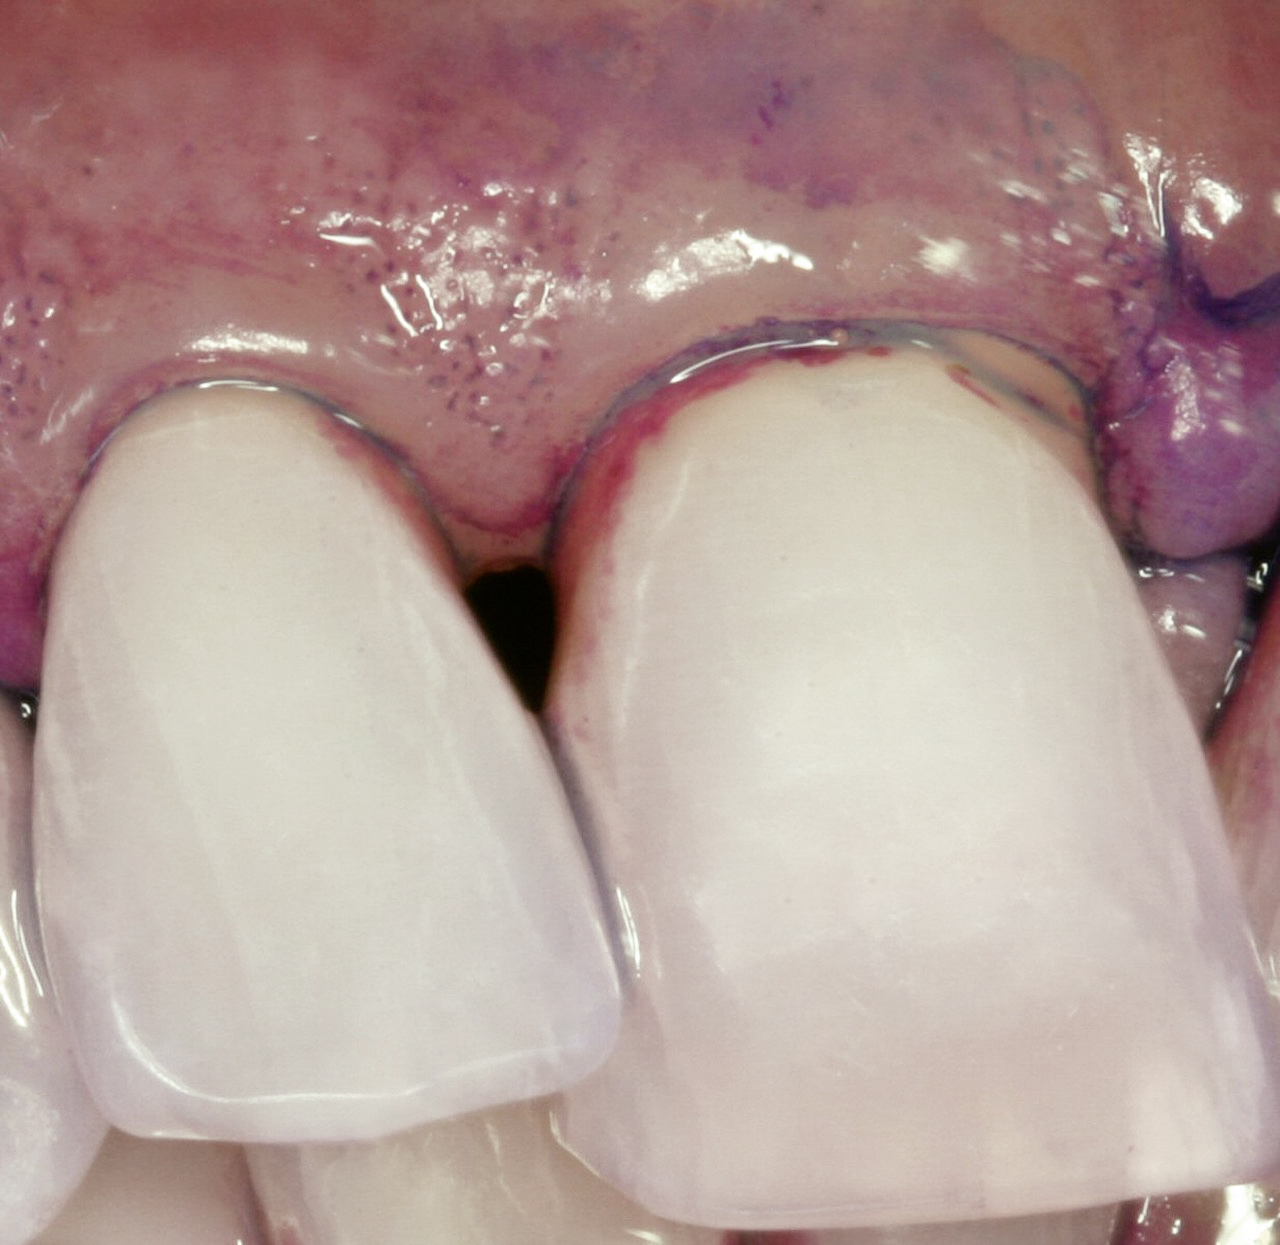

Eine erfolgreiche Behandlung der parodontalen Entzündung kann nicht nur die lokalen Symptome der Erkrankung des Zahnhalteapparats und damit Zahnverlust vermindern (s. Abb. 3 u. 4), sondern auch die Stoffwechseleinstellung verbessern. Die Reduktion des HbA1c-Werts lag bei Typ-2-Diabetikern drei Monate nach einer nichtchirurgischen Parodontitisbehandlung zwischen 0,4 und 0,5 Prozent, was durchaus nennenswert ist.

Eine erfolgreich behandelte Parodontitis kann zurückkehren

Auch wenn die Parodontitis erfolgreich behandelt wurde, kann sie zurückkehren, wenn die bakteriellen Zahnbeläge durch die Patienten nicht effektiv in Schach gehalten werden. Wer einmal wegen Parodontitis behandelt wurde, muss deshalb ein Leben lang sorgfältig nachbetreut werden: Mindestens einmal pro Jahr müssen alle Zahnfleischtaschen nachgemessen werden. Es muss regelmäßig überprüft werden, wie gut die häusliche Mundhygiene funktioniert, und sich vertiefende Zahnfleischtaschen müssen frühzeitig nachbehandelt werden.